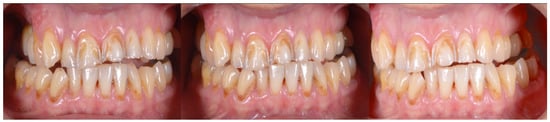

2.2. Clinical Example